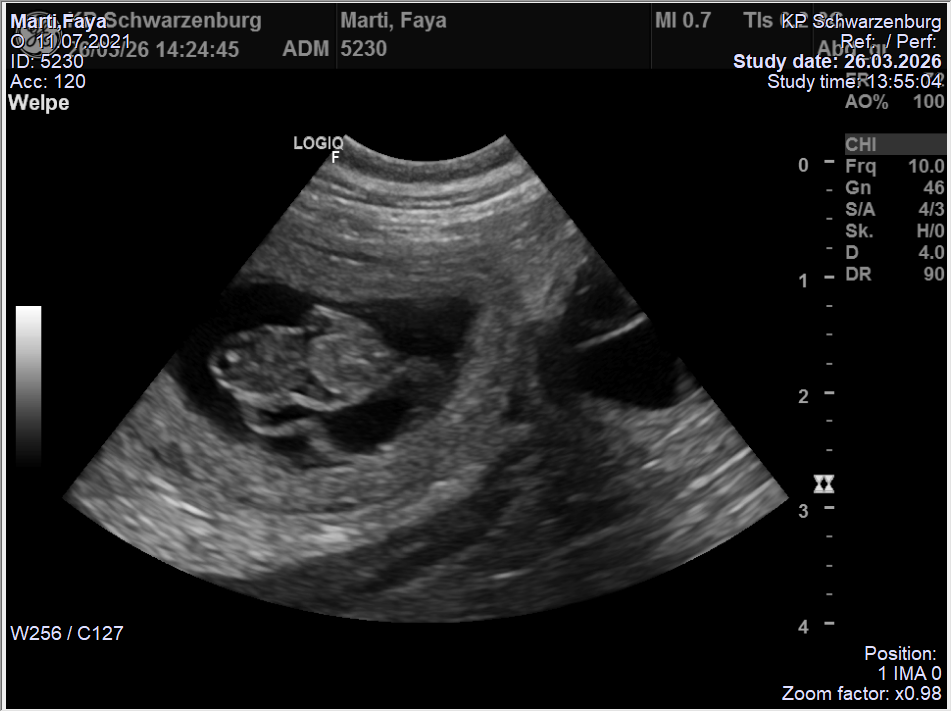

Trächtigkeit

Faya ist in ihrer Trächtigkeit eher gemütlich unterwegs.

An Tag 53 wiegt sie 16.1 kg bei einem Normalgewicht von 12.5 kg.